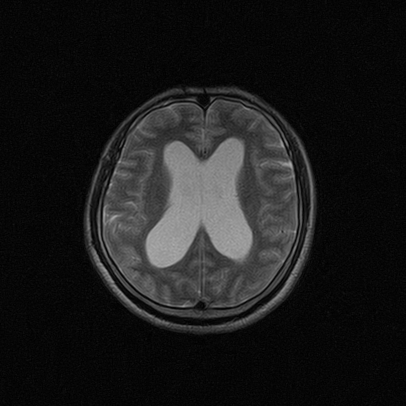

标题: MRI2064:少见病例。男性52,视力下降多年。

四脑室区见混杂信号占位影,脑室系统扩张明显,临近结构显著受压称位,患者52岁,多考虑室管膜瘤可能性大

考虑第四脑室室管膜瘤并阻塞性脑积水。

考虑第四脑室室管膜瘤并梗阻性脑积水;部分性空蝶鞍;左侧上颌窦粘膜下囊肿。

考虑第四脑室室管膜瘤【血供丰富血管母细胞瘤可能】并梗阻性脑积水;部分性空蝶鞍;左侧上颌窦粘膜下囊肿。

比较典型的脉络丛乳头状瘤并脑积水,鉴别小脑蚓部血管母细胞瘤。